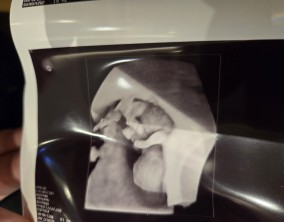

심장소리 이후, 함께 웃게 된 임밍아웃

유정원장님 치료 과정 내내 항상 따뜻하게 진료해 주셔서 감사한 마음이 큽니다. 덕분에 불안한 순간에도 마음을 다잡고 치료를 이어갈 수 있었습니다.